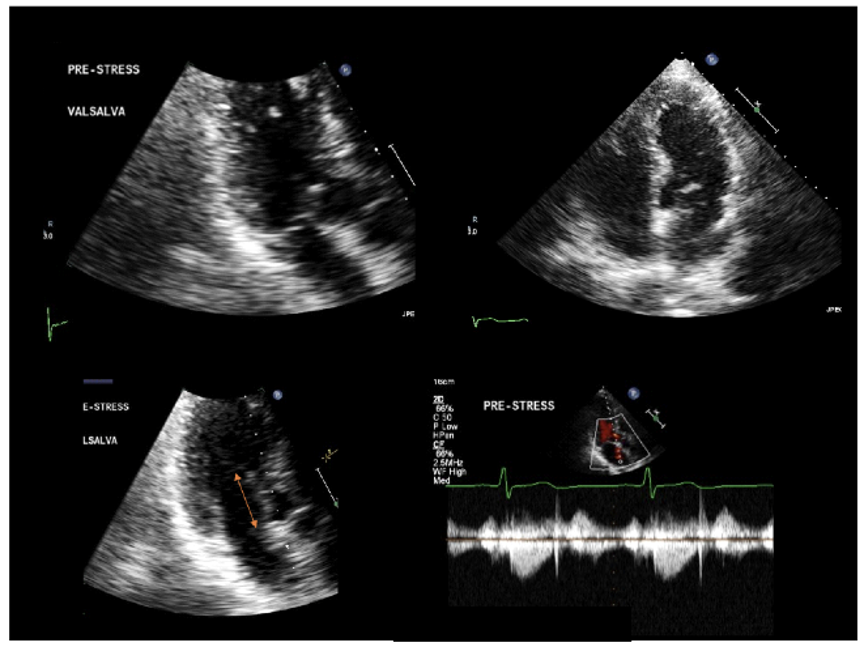

No Resting LVOT Gradient

Transthoracic echocardiography in a 60-year-old man with angina and a new systolic murmur. Panels show systolic anterior motion (SAM) at rest without mitral septal contact, mild septal bulge, normal 4-chamber-view systolic function, long mitral anterior leaflet measuring 30 mm, without resting LVOT gradient. Source: NYU Langone Health

Stress Echocardiography

After exercise stress echocardiography, an LVOT gradient of 50 mm Hg, due to SAM and mitral-septal contact, were detected. Mild septal bulge and normal systolic function were appreciated. Source: NYU Langone Health